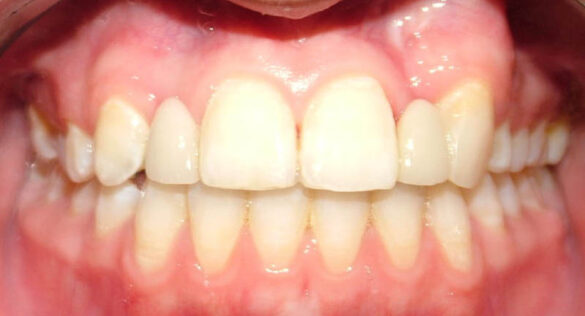

La momentul prezentării în clinică, în decembrie 2002, pacienta avea 8 ani şi o lună şi suferea de fibroză chistică şi de o deficienţă de dezvoltare a etajului mijlociu al feţei. Aceasta prezenta o anomalie de clasa I care mima o anomalie de clasa a III-a. Incisivii centrali, laterali şi caninii temporari maxilari, precum şi molarii prim şi secund de pe partea stângă erau în ocluzie inversă. În plus, pacienta prezenta coloraţii ale dinţilor de etiologie idiopatică (fig. 1). Autorii au considerat coloraţiile ca fiind de suprafaţă, extrinsece şi nu determinate de fibroza chistică, dovadă îndepărtarea acestora prin periaj profesional. Radiografia panoramică efectuată cu 6 luni înainte de prezentarea în clinica stomatologică relevă anodonţia incisivilor laterali superiori şi a premolarului secund drept inferior, ca şi posibila incluzie a caninilor maxilari, în special a celui stâng (fig. 2).

În aprilie 2009, după 37 luni de tratament, au fost îndepărtate aparatele fixe (fig. 6). Pentru contenţie, s-a aplicat un retainer fix colat pe faţa linguală a celor şase dinţi frontali inferiori şi o placă palatinală Hawley care încorporează dinţi acrilici în dreptul incisivilor laterali pentru a menţine un aspect estetic până când medicul protetician va putea realiza punţile dentare. În plus, s-a utilizat un arc vestibular care să consolideze contenţia şi care să permită aplicarea unor forţe uşoare, cu direcţie linguală, dacă este necesar.25 Croşetele ”în deget” sunt situate distal de incisivii centrali maxilari şi mezial de caninii superiori, pentru a permite o deplasare discretă mezio-distală a dinţilor, dacă este necesar (fig. 7).Înainte de îndepărtarea aparatului, a fost consultat medicul protetician. S-a pus problema dacă pacienta ar avea dificultatea de a purta pe termen lung un aparat mobil de contenţie, din cauza dificultăţilor de respiraţie şi a tusei, asociate cu fibroza chistică. În plus, din cauza anodonţiei de incisivi laterali superiori, osul alveolar este dezvoltat insuficient şi prezintă, astfel, dimensiuni prea reduse pentru inserarea implantelor dentare; procedura de augmentare a ţesuturilor moi şi dure ale crestei alveolare ar fi inevitabilă. Vârsta pacientei şi creşterea şi dezvoltarea corespunzătoare au fost, de asemenea, luate în considerare.19 Ortopantomograma finală relevă anodonţia molarilor de minte inferiori şi a celui superior drept pe lângă anodonţia incisivilor laterali maxilari şi a premolarului secund drept inferior. De asemenea, se remarcă aplatizarea rădăcinilor incisivilor centrali maxilari, care era prezentă şi pe radiografia efectuată înainte de tratament (fig.8).